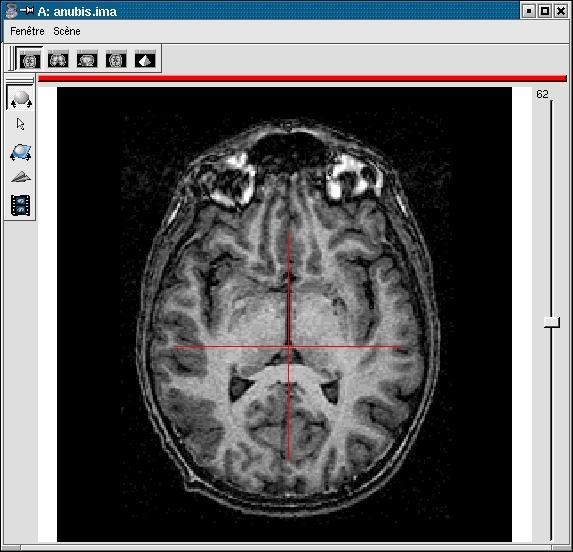

If your image is not spatially normalised, Anatomist will help you to click on the 3 or 4 points of interest.

- If the volume is not already visible, click on the edit button of one of the point parameters to have Anatomist display it

- Set the Anatomist view so as to see the point (use the slice slider) and click in it on the wished point.

- When the cursor position is good, click on the button of the 3D point in BrainVISA: the position is transfered from Anatomist to BrainVISA.

You have to select 3 points (you can use a sagittal slice if you prefer):

- Intersection of anterior commissure with interhemispheric plane;

- Intersection of posterior commissure with interhemispheric plane;

- Any point of the interhemispheric plane not aligned with the previous ones.

- Optionally, any point of the left hemisphere. Specifying this point is not mandatory, it is only useful to detect a possible orientation problem on the input image. Be careful, axial and coronal views in Anatomist are in radiological convention by default (left and right are flipped).

Anterior commissure:

Posterior commissure:

Inter-hemispheric plane:

Point of the left hemisphere (on the right on axial slices displayed in radiological convention):